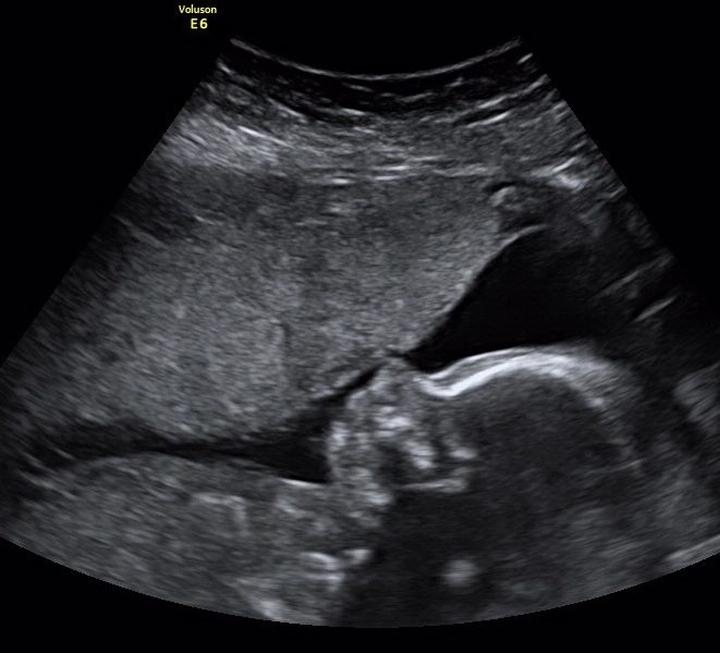

Badanie USG połówkowe z pewnością powinno zajmować jedno z najważniejszych miejsc na liście przyszłych mam! Kto nie chciałby w końcu zobaczyć swojego malucha w brzuszku? Dlatego warto zastanowić się, kiedy zarezerwować ten niesamowity seans. Zaleca się, aby wykonać badanie w momencie, gdy dziecko zaczyna ważyć mniej więcej tyle co średniej wielkości grejpfrut, co zazwyczaj odpowiada połowie ciąży. Termin ten, pomiędzy 18 a 22 tygodniem, to czas, kiedy mały pasażer ma wystarczające rozmiary, co pozwala lekarzowi na dokładną ocenę jego stanu. Kto by pomyślał, że takie maleństwa potrafią tak szybko rosnąć!

W praktyce najlepiej umówić wizytę po ukończeniu dwudziestego tygodnia, ale przed 22. To właśnie wtedy organy Twojego dziecka będą na tyle rozwinięte, iż lekarz bez trudu oceni jego budowę. W tym okresie istnieje możliwość dokładnego zmierzenia młodego człowieka i przyjrzenia się mu z każdej strony. Lekarz będzie mógł także sprawdzić, czy na pewno nie jest mutantem z krainy „paleontologicznych” obrazków! Dlatego, jeśli nie wpiszesz tej daty w kalendarz, możesz niestety przegapić ten ekscytujący moment!

W trakcie USG połówkowego lekarz stanie się archeologiem, odkrywającym tajemnice Twojego dziecka. Zajmie się różnymi pomiarami, takimi jak obwód głowy, długość kości udowej i wiele innych. To pełnowymiarowy przegląd, który pokaże, czy maluszek rozwija się zgodnie z planem. Jeżeli masz ochotę poznać płeć, nie wahaj się domagać od lekarza gorliwego zajęcia się także „sprawami płciowymi” – w końcu każdy rodzic pragnie wiedzieć, czy w przyszłości czeka go męski lub żeński „kolorowy” remont w pokoju!